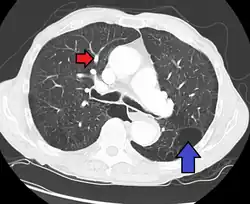

CT scan

Signs of pulmonary hypertension on CT scan of the chest are:

- Enlargement of the pulmonary trunk (measured at its bifurcation). It is, however, a poor predictor of pulmonary hypertension in patients with interstitial lung disease.[63]

- Increased ratio of the diameter of the main pulmonary artery (pulmonary trunk) to the ascending aorta (measured at its bifurcation).

- Increased diameter ratio of segmental arteries to bronchi. This finding in three or four lobes, in the presence of a dilated pulmonary trunk (≥29 mm), and absence of significant structural lung disease confers a specificity of 100% for pulmonary hypertension.[63]

- Mural calcification in central pulmonary arteries is most frequently seen in patients with Eisenmenger's syndrome.[63]